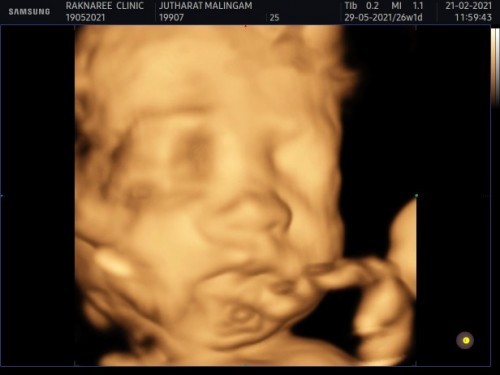

แม่ได้ไปอัลตร้าซาวด์4มิติที่คลินิกแห่งนึง ผลปรากฏว่าน้องแข็งแรงดี ทุกอย่างเป็นปกติ แต่แม่มีเนื้องอกที่หน้าผนังมดลูก ซึ่งตกใจเล็กน้อยเพราะหมอที่ฝากครรภ์ไม่ได้กล่าวถึงเรื่องนี้เลย และหมอคลินิกแนะนำว่าหลังคลอดเสร็จ1เดือนให้อัลตร้าซาวด์อีกครั้งเพื่อดู ผลที่ตามมาอาจจะคลอดก่อนกำหนดเพราะเนื้องอกโตตามอายุครรภ์ กำหนดคลอด29พฤษภาคม64 #ขอกำลังใจแม่ๆหน่อยค่ะ

Đọc thêmบ้านนี้คุณหมอฝากครรภ์ไม่ได้แจ้งเลยค่ะ อัลตร้าซาวด์ทุกเดือนก็ดูแค่น้องและก็ไม่ได้แจ้งอะไรเลย เลยไปซาวด์แบบ4มิติตอน26วีค หมอจึงได้แจ้งค่ะว่ามีเนื้องอก